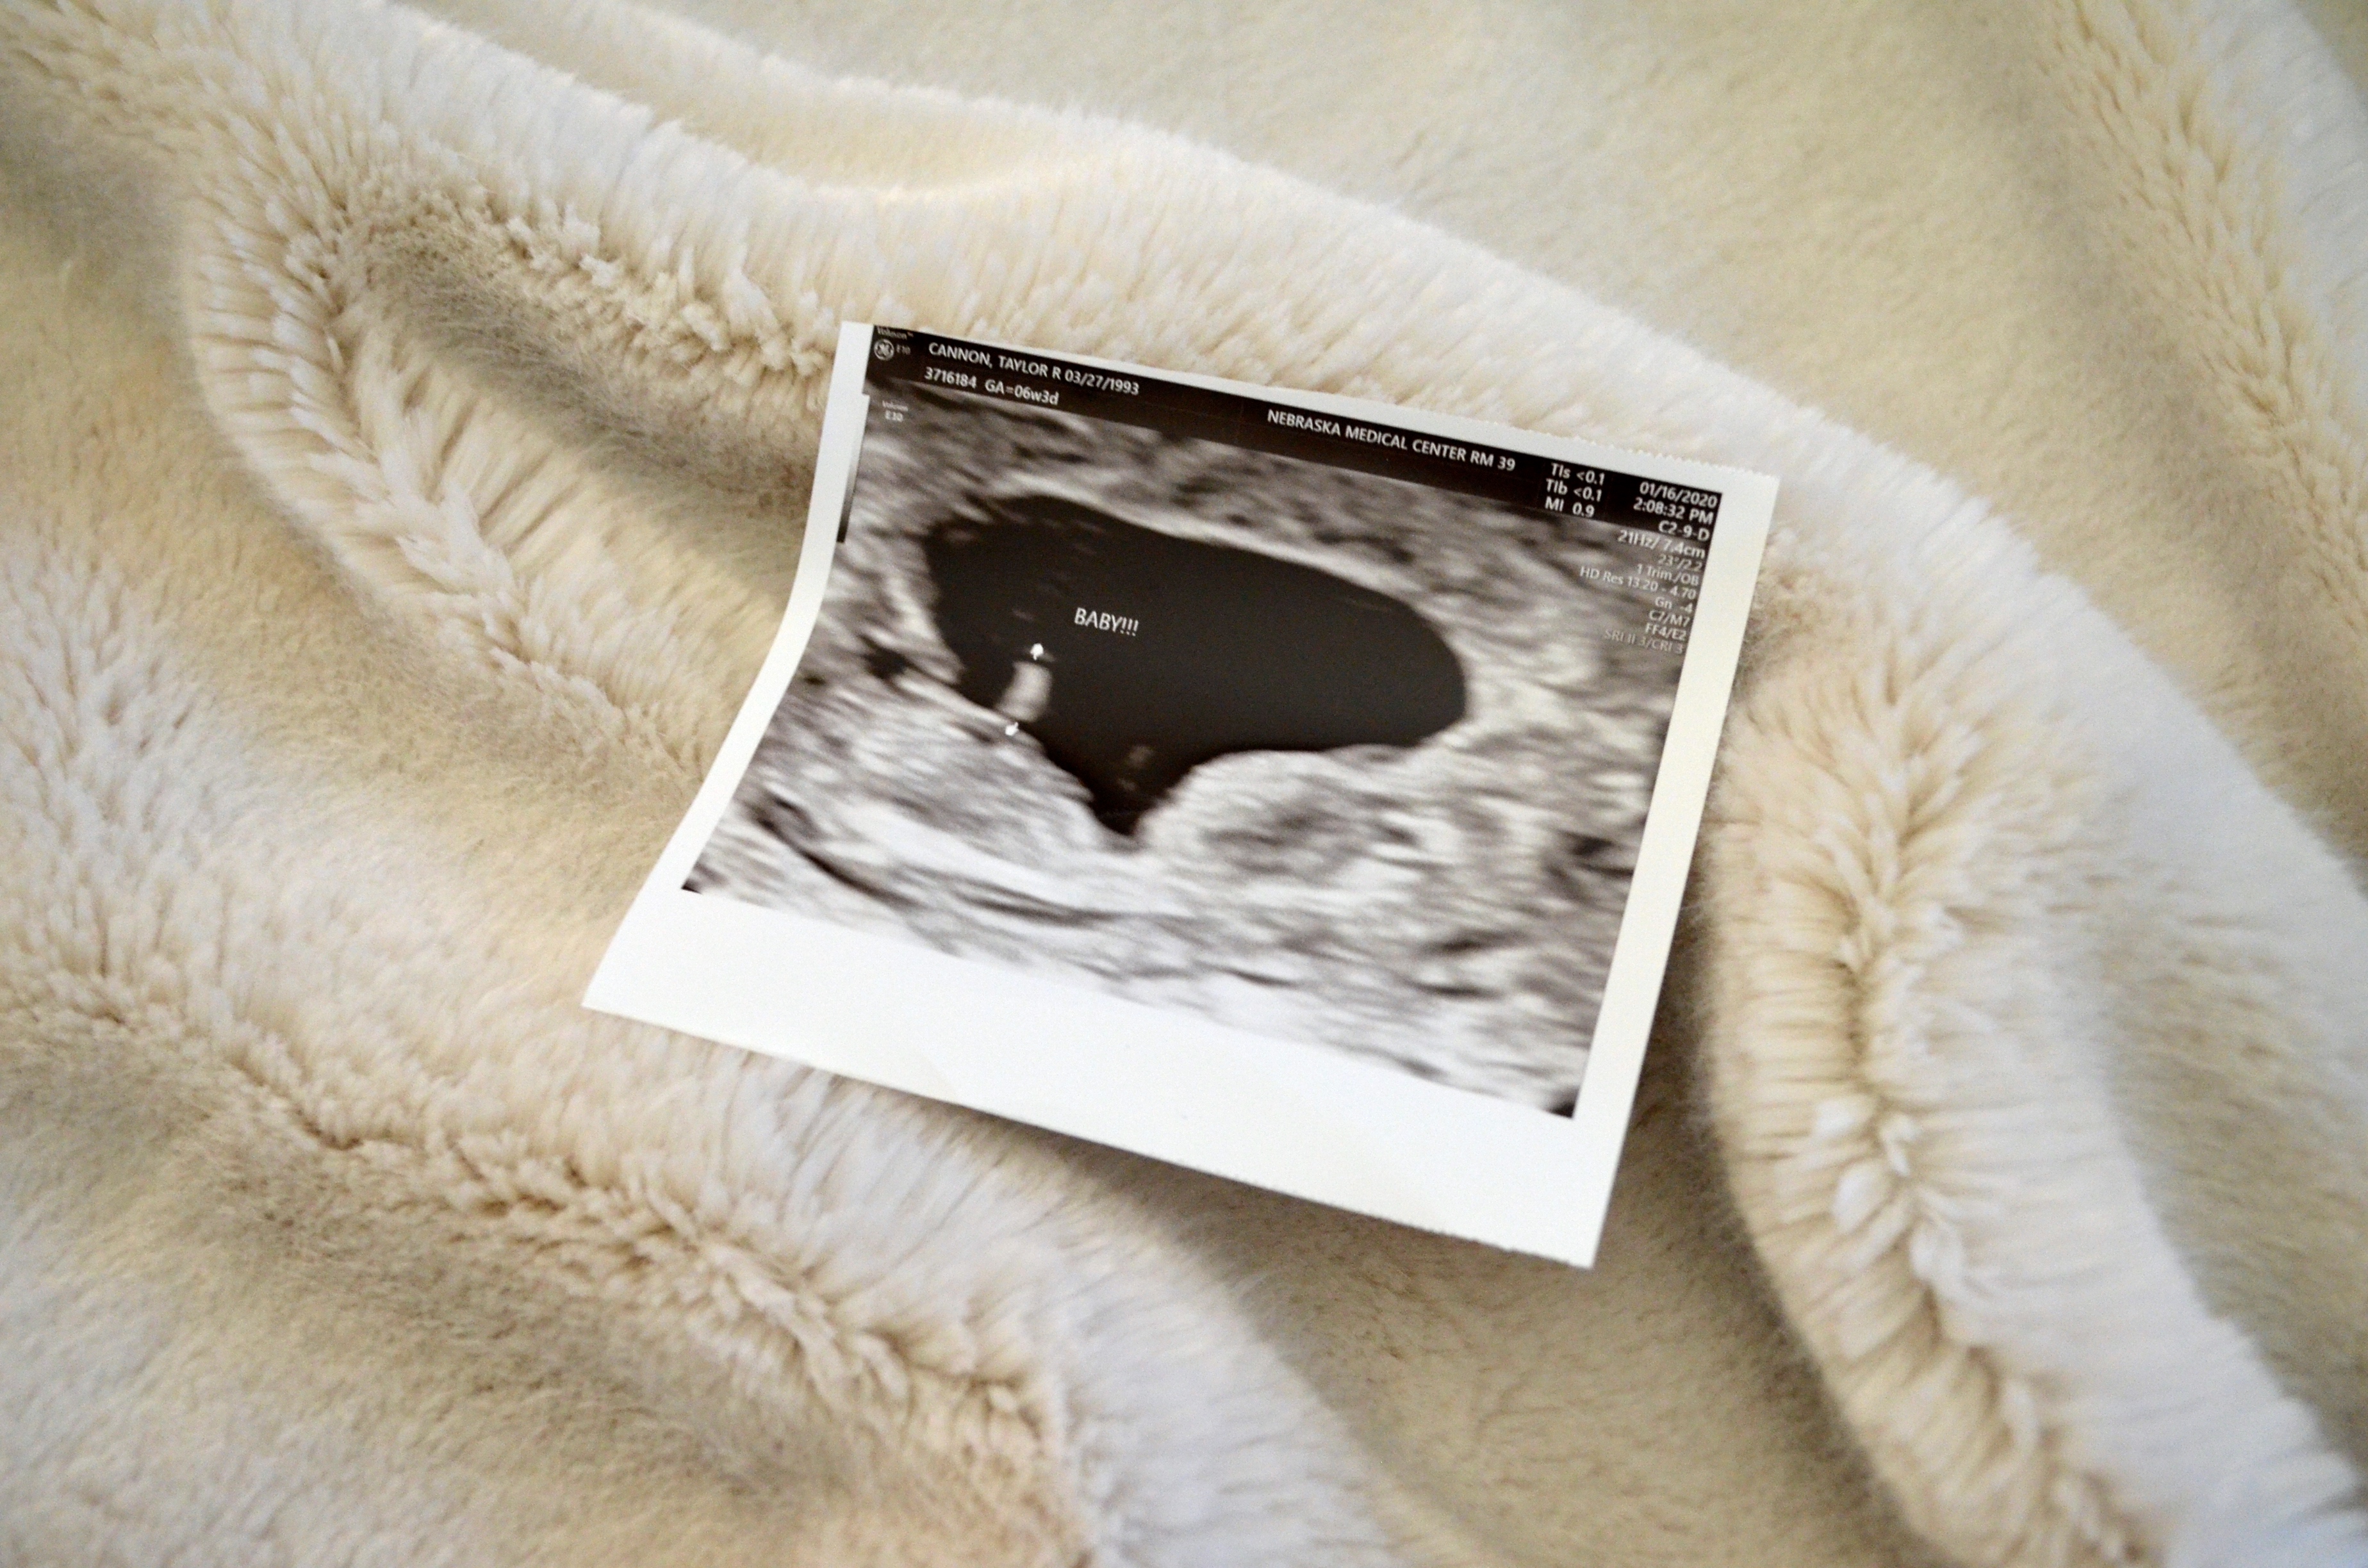

As a quick summary, I found out I was pregnant in mid-January. On February 4th at an ultrasound appointment I was told there was no heart beat to be found. A week later I took a trip to the ER for excessive bleeding. After invasive and painful exams I was told that should be the end of it. I was sent home and told the bleeding should stop within a few days.